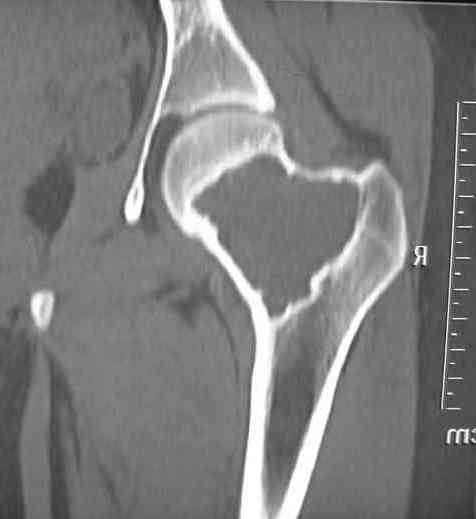

Больная Л., 23 года.

Из анамнеза:со слов больной в 2006 г. появились боли правой н/конечности, обратилась поместу жительства к хирургу, было выполнена МРТ поясничного отдела позвоночника,назначено физиолечение.

Через 2 месяца боли прекратились, через 4 месяца рецидив болевого синдрома. С 2006 – 2010 проводилось консервативное лечение по поводу остеохондроза поясничного отдела позвоночника. В октябре 2010 г. боли усилились. Выполнены Ro и КТ правого тазобедренного сустава, выявлен очаг патологической перестройки. Была направлена на консультацию в УНИИТО.

В УНИИТО виюне 2011 г. поставлен дифференциальный диагноз между фибромой, солитарной костнойкистой и гигантоклеточной опухолью.

Наши предложение по выбору лечения:

1) эндопротезирование тазобедренного сустава;

2) при выявлении ОБК – заполнение полости костным цементом;

3) в случае фибромы – заполнение полости аллокостью.

Вариант пластикиа утокостью не подходит, т.к пациентка субтильного телосложения.